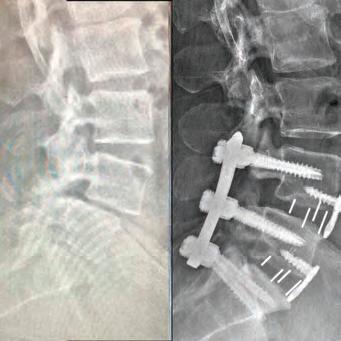

Inspired by the patients he’s cared for there, Dr. Courtney made education a priority. He was salutatorian of his high school class and went on to graduate summa cum laude from Northeast Louisiana University. While at Louisiana State University Medical School, he utilized his summer to perform spine biomechanical tests on human spine cadavers utilizing pedicle screws. Considered cutting edge biomechanics and technology at that time, most spine surgeons didn’t even know they existed yet. However, Dr. Courtney performed one of the first biomechanical tests on those implants. It was a feat that earned him the Howmedica Biomechanic Award and the Louisiana Orthopedic Association Award. He also placed fourth in the World Congress for Student Research Competition.

Dr. Courtney’s residency at Texas A&M University Medical Center and further specialty training through a fellowship at Florida Neck & Back Institute in Gainesville, Florida, additionally cemented his strong medical foundation. From there, he continued to gain more knowledge and insight on how to help his patients with useful tools, while recognizing there was room for much improvement in the tools at hand.

This realization inspired Dr. Courtney to design, develop, biomechanically test, complete FDA testing and oversee quality control and

validation on a host of tools he created. To date, Dr. Courtney has developed nine spinal product lines and obtained nine patents and 14 trademarks on spine related products.

When he’s not traveling the country training other physicians on how to utilize his products, Dr. Courtney dedicates himself to the patients of his own medical practice, Advanced Spine Center.

Led by Dr. Courtney, the skilled team at Advanced Spine Center cares for patients with neck and back pain using a wide array of the most state-of-the-art tools and techniques—from conservative physical therapy and injection therapy—to advanced pain management, as well as surgical intervention. We employ the latest in minimally invasive spine surgeries, in addition to cutting-edge replacement technology. Incorporating both high tech and high touch, we get our valued patients back to their lives so they can enjoy all the activities they love.